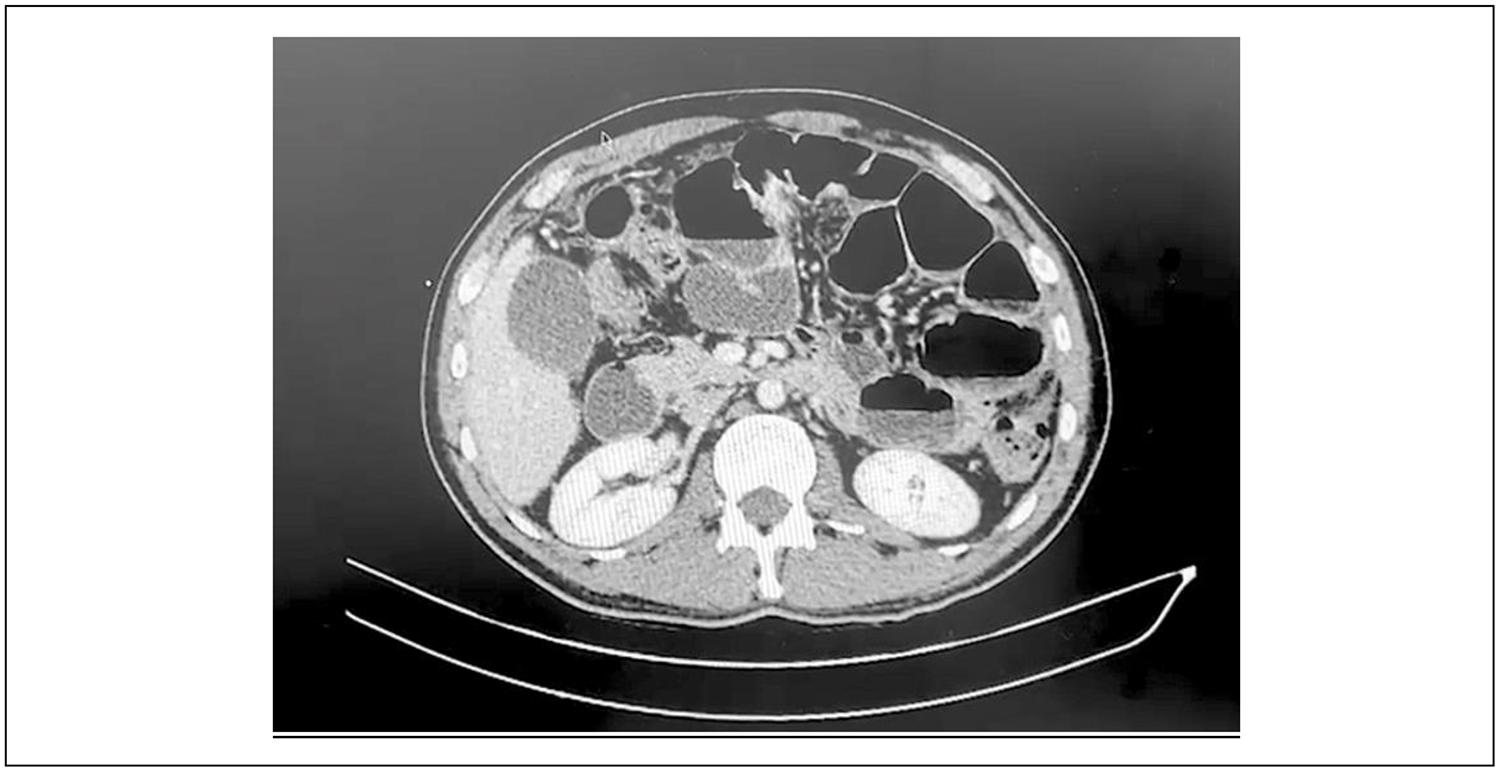

Durante el año 2024, el paciente consulta en dos oportunidades por síndrome suboclusivo, que revierte con tratamiento médico. Sin embargo, posteriormente concurre a emergencia por vómitos persistentes, asociados a detención del tránsito, con eliminación de gases. En este contexto, se realiza tomografía que evidencia oclusión parcial del intestino delgado secundaria a implantes peritoneales (Figura 1).

Figura 1. Tomografía de abdomen y pelvis que muestra asas delgadas distendidas, con niveles hidroaéreos, pared edematizada y carcinomatosis peritoneal extensa.